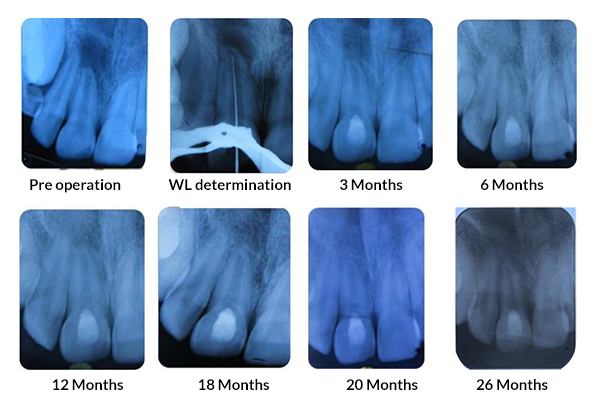

PRF Mediated REP in 21 with 26 Months Follow Up

Complete Bony Healing, Apex Closed, Lateral Dentinal Wall Thickened, PDL Apically

PRP Mediated REP in 21 with 18 months follow up

Bone healing, Apical PDL formed, Apex Closed, Calcific Bridge formed in 21.

Vitality Positive

PRF Mediated REP in 22 with 18 months Follow up

Complete Bony Healing, Calcific Bridge Formed.